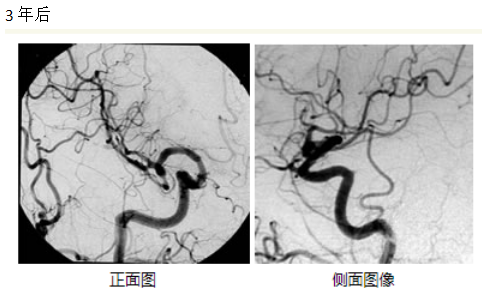

治療結(jié)果根據(jù)病變的大小和部位有很大的差異,據(jù)報道,γ刀治療的直徑3cm以內(nèi)的腦動靜脈畸形的情況下,3年后的五年生存率約為60%-90%前后。下圖為伽馬刀治療成功并完全阻塞的典型案例-伽瑪?shù)赌X血管造影術(shù)。